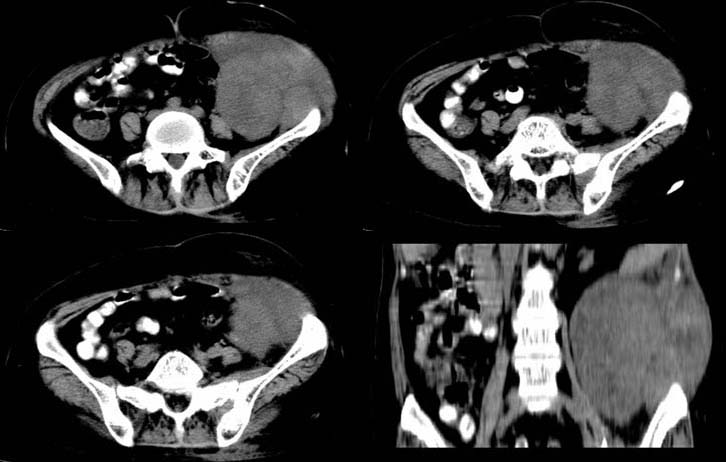

以下是引用qian在2008-6-12 20:27:00的发言:[br]肿块的最大直径位于左侧腹壁,肿块内的密度不均匀,与腹腔内的脏器的界限清楚,考虑为恶性病变,纤维肉瘤可能大。

以下是引用312nanyang在2008-6-12 21:39:00的发言:[br]考虑为来源于腹壁的肿瘤,恶性可能性大。左侧输尿管上段积水

以下是引用zsl6918在2008-6-12 20:32:00的发言:[br]符合来源于腹壁的恶性肿瘤。

以下是引用gaoshengjiang在2008-6-12 20:23:00的发言:[br]考虑来源腹壁肌肉的纤维肉瘤可能。